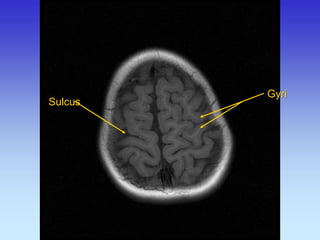

Gyri

Sulci

Sulcus